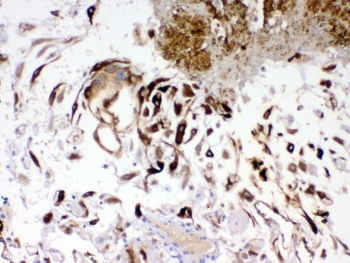

IHC testing of FFPE human placenta tissue with IGFBP1 antibody. Required HIER: steam section in pH8 EDTA buffer for 20 min and allow to cool prior to testing.